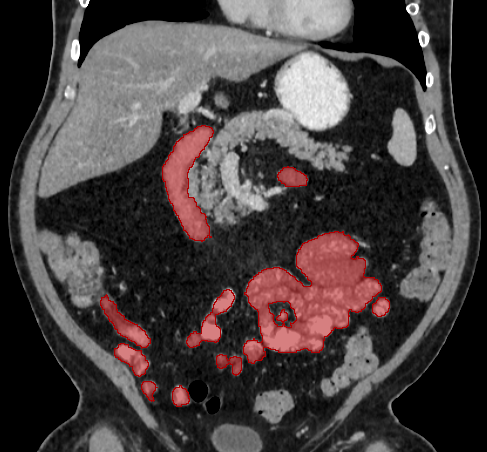

Over the years, there have been attempts to develop automatic methods for small bowel segmentation, especially using deep learning. The small bowel was included in segmenting multiple organs-at-risk for radiotherapy treatment planning of affected tissues, such as pancreatic and cervical cancers, in CT scans [8, 9, 13]. Although the results obtained for the small bowel are reasonable, some of their data included only the part of the small bowel that is closest to the target area, which needed to be dose-evaluated [8, 9]. In [13], the rough bowel location was detected instead of performing pixel-accurate small bowel segmentation. There have been only a few previous works dedicated solely to automatic small bowel segmentation [12, 14, 21]. While the specific anatomic relationship between the mesenteric vasculature and the small bowel is used to guide the small bowel segmentation in [21], a cylindrical shape constraint is applied during training of the small bowel segmenter in [14]. Although each of the works showed reasonable performance for particular datasets, their generalizability across different datasets was not evaluated. A CT scan is acquired using a specific imaging protocol depending on the purpose of the investigation, which includes the use of different contrast media and scan timing. Thus, the appearance of the small bowel may be different across datasets as exemplified in Figure 1. It is observed in our experiment that, when trained on one dataset, the model does not generalize well to another dataset due to the domain shift (section 3).

In this paper, we present a novel unsupervised domain adaptation method for small bowel segmentation, which is based on feature disentanglement. Although the absolute intensity values in CT scans (Hounsfield units) carry important information on specific substances of the human body, thus could provide a clue of being specific tissues and organs, they may be variable according to the imaging protocol. Figure 1 shows example CT scans that were acquired with and without oral contrast administration. The absolute intensity values are no longer a strong clue for the small bowel when we train and test across the datasets. Non-intensity features like texture and shape may be more useful. For example, local textures of the valvulae conniventes, which are circular folds on the inner surface of the small bowel, are more recurrent across the datasets.

A

B

B

C

C

D

D